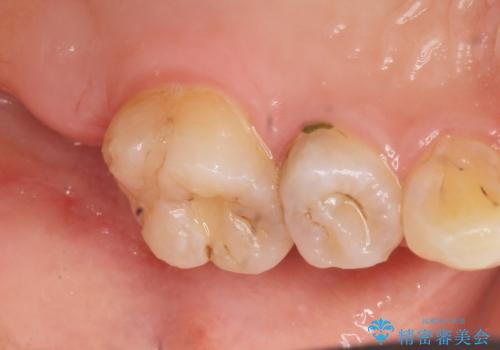

フロスを通すと臭い 歯と歯の間の虫歯 セラミックインレー 30代女性

- 歯と歯の間の虫歯治療を希望された患者様です。

フロスを通すと臭いのが気になるとの事でした。

精査したところ、左上の奥歯の間(左上56間)にう蝕を認めました。

う蝕を丁寧に除去したのち、セラミックインレーによる修復を行いました。